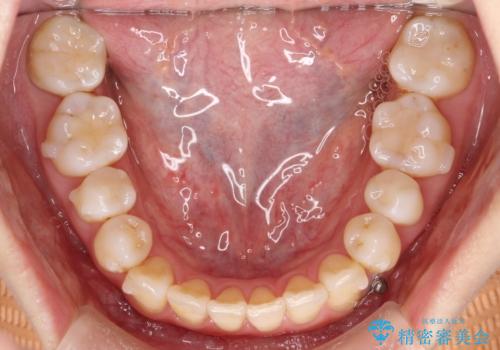

初診時の歯並びの状態としては、上下ともに前歯部中心としたの中等度のがたつき(叢生)があり、全特に左上の前歯は1本だけ引っ込んでおり、犬歯は外に飛び出した状態でした。

抜歯は行わず上顎の奥のスペースを利用して歯をスライドする方法の他に歯列弓の拡大やディスキング(歯と歯の間の隙間を作る処置)を行い叢生を改善しましています。

見た目、嚙み合わせ及び、治療期間や施術内容に大変ご満足いただきました。